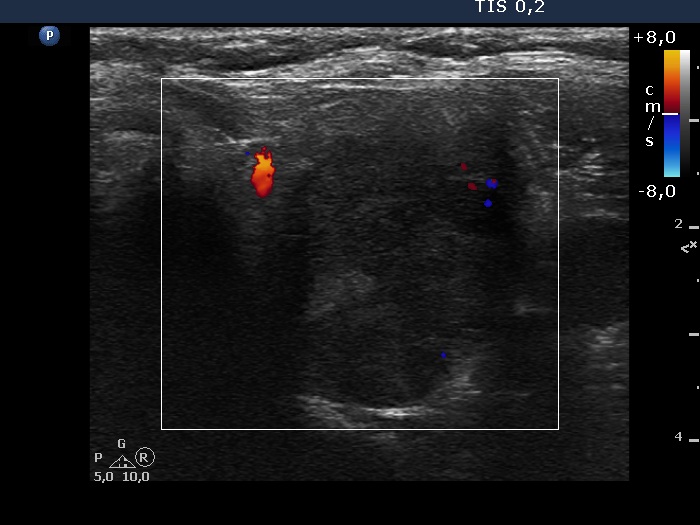

Follow-up examination six years after the first visit (ultrasonographic picture 11)

Lower part of the left lobe, transverse scan, color Doppler mode. The nodule is almost avascular.